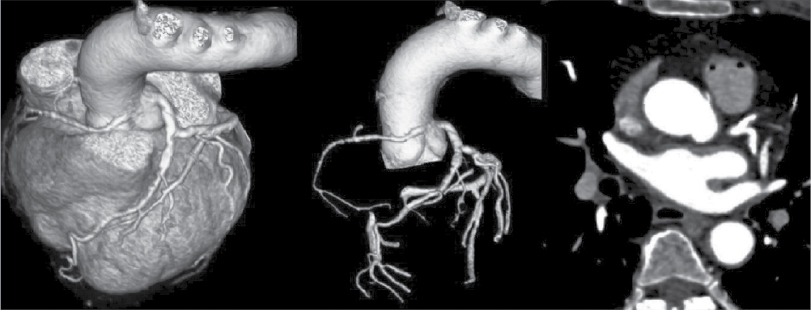

At Nizam’s Institute of Medical Sciences (NIMS), Hyderabad, 770 patients underwent CT-conventional coronary angiography (CAG), on 128-slice single source MDCT (SOMATOM Definition AS ± SEIMENS) during the last 3 years (unpublished data). On analysis, coronary artery anomalies were found in 23 patients (3%). Their ages ranged from 25 to 82 years. Majority of the cases were in 51 to 60 years age group. Among them, 17 were males. The most common anomaly seen was high take-off of coronary arteries, seen in 10 cases. Of them, 2 were having high origin of right coronary artery (RCA) (Fig. 1), 7 were having high origin of left main coronary artery (LMCA) and one was having high origin of both coronary arteries with acute kink at the origin of RCA. Anomalous origin of coronary artery from opposite sinus was seen in 8 cases (Figs. 2-5). RCA from left coronary sinus with interarterial course between aorta and right ventricular outflow tract was seen in 5 cases. Anomalous origin of left coronary artery (LCA) from right coronary sinus with interarterial course between aorta and right ventricular outflow tract was seen in 2 cases. Anomalous origin of left circumflex artery (LCx) from right coronary sinus with retroaortic course was seen in 1 case (Fig. 6). Separate ostia for left anterior descending artery (LAD) and LCx was noted in 3 patients (Figs. 7 and 8). Shepherd crook deformity of proximal segment of RCA was seen in 1 patient. Super-dominant RCA with absent LCx was seen in 1 patient (Fig. 9).

Figure 2. VRT and axial images of a patient (55/F) showing RCA originating from left coronary sinus of Valsalva. Course of RCA is interarterial.

Figure 3. VRT and axial images of a patient aged 59/M depicting the origin of LCA from RCA having interarterial course.

Origin of coronary artery or branch from the opposite or noncoronary sinus is another anomaly that is commonly observed. These anomalies are classified into 4 types. One is interarterial course between aorta and pulmonary artery. Second one is retroaortic course. Third is prepulmonic and septal or subpulmonic course. The interarterial course is clinically important as it is associated with sudden death.5 Fujimoto et al, in their series of 5,869 cases, noted that 29 cases had opposite coronary sinus and in 27 of these cases RCA arose from left coronary sinus.4 All these cases had interarterial course. It is reported that 30% of these have sudden cardiac death. Anomalous origin of coronary artery from opposite sinus was seen in 8 cases accounting for 1.04%. RCA from left sinus were 5 and LCA from right coronary sinus were 2 with interarterial course. In 1 case, LCx was arising from right coronary sinus with retroaortic course.